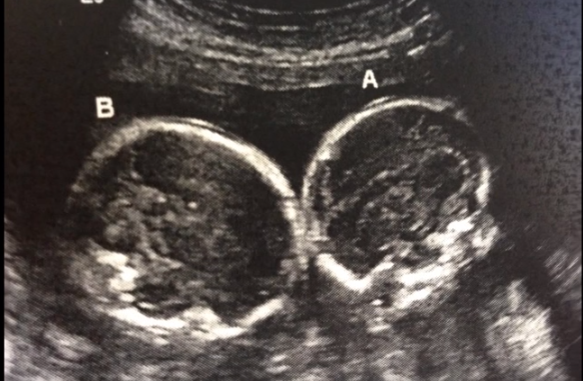

Normalement, une grossesse gémellaire est bichoriale (deux placentas) et biamniotique (deux poches amniotiques). Mais en fonction du moment où l’œuf fécondé s’est divisé, la grossesse peut-être monochoriale (un seul placenta) et biamniotique (deux poches amniotiques). Ou encore, comme dans le cas de Lisa, ses jumelles sont monochoriales et mono-amniotiques. Pendant la grossesse, les jumeaux partagent le même placenta et la même poche amniotique. Seulement 1% des grossesses gémellaires monozygotes sont des grossesses monochoriales et mono-amniotiques.

On peut déceler une grossesse monozygote, monochoriale et mono-amniotique dès l’échographie de la 12ème semaine. Pendant toute la grossesse, la maman devra être suivie de près, dans une maternité de niveau 3, pour éviter toutes les complications et, le plus souvent, devra rester alitée une bonne partie de sa grossesse. Un accouchement par voie basse,même s’il est possible, présente en effet des risques, il est donc plus fréquent que les jumeaux naissent par césarienne au bout de la 32ème semaine de grossesse.